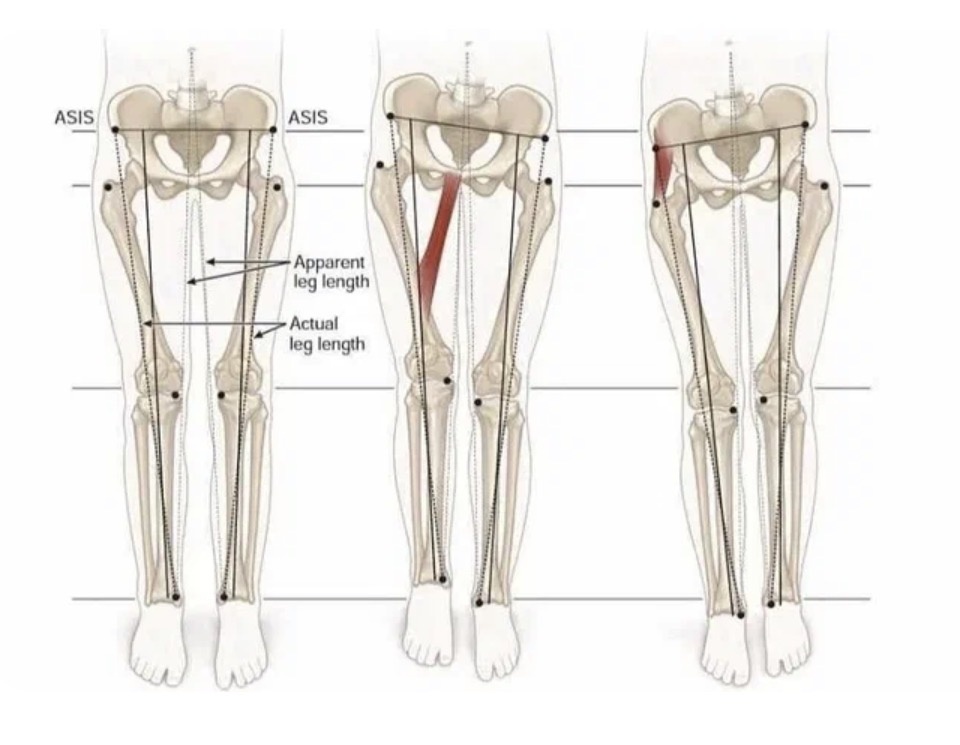

Первое, что нужно понимать, это разницу в причине - то ли одна нога действительно короче другой (абсолютная разница, измеряемая), то ли просто тело наклонено в сторону, из-за чего одна нога просто пошла вверх вслед за тазом (относительная разница).

Наглядная схема